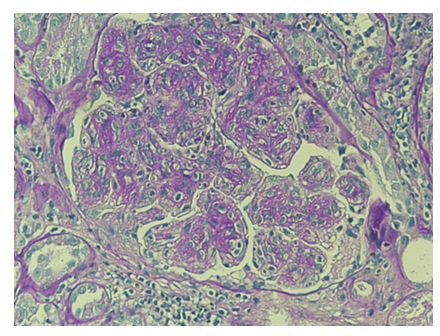

For further diagnostic investigation of nephrotic syndrome, a renal biopsy was performed (june 2023), which showed mesangial hypercellularity with interposition along the wall of the glomerular capillaries. (Figure 1,2). Immunofluorescence revealed finely granular, peripheral, segmental, diffuse positivity for C3 (++) and C1q (+), and negative IgA, IgG, IgM, fibrinogen and kappa and lambda light chains. The patient was diagnosed with C3 glomerulopathy.